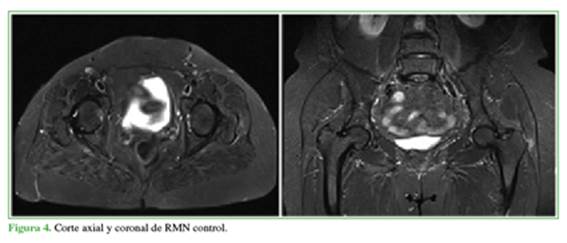

La RMN indica que hay ruptura de tipo completo de la inserción del glúteo medio en su porción posterior y lateral, con disrupción de las fibras que se extiende hacia la porción anterior de la unión miotendinosa, con compromiso hemorrágico al interior de las fibras musculares y avulsión ósea completa en el sitio de inserción, en la región lateral del glúteo medio. Y se señala que debe tenerse en cuenta la hiperintensidad que rodea al glúteo medio izquierdo por tendinopatía y tendinitis versus la lesión parcial asociada, que se debe correlacionar con el mecanismo del trauma (Figura 2).